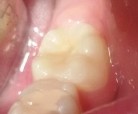

Bệnh nhân: Ng. Minh T. 9 tuổi. Răng 36, mã BA 13519/17

Sau ba tháng. ICDAS:2; Di: 22 | Sau 12 tháng. ICDAS:0; Di: 09 | Sau 18 tháng. ICDAS:0; Di: 05 |